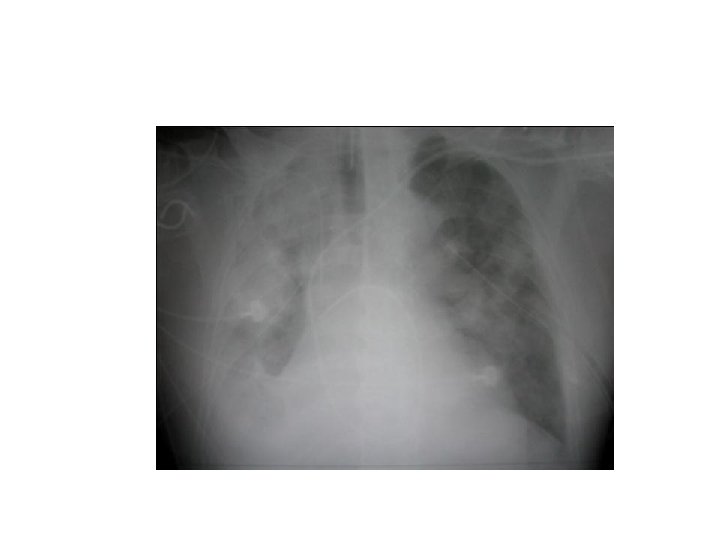

Left bronchus syndrome , Next slide Plzzz =) Notice , the Trachea is pulled to left side. . WHY ? cuz of fibrosis there is loss of space , loss of ventilation in the left side , the left lung is smaller in size , infective , bronchioectatic , it will pull the trachea toward it.

Left bronchus syndrome : Chronic condition , it is the end sequelae ﺍﻟﻨﺘﻴﺠﺔ ﺍﻟﻨﻬﺎﺋﻴﺔ of lung destruction due to TB In the previous slide , notice the bronchioectatic changes all over the lung ! Rt lung : pt still can breath from it , although it has apical scarring , Rt upper zone infiltration. Lt Lung : has Abcess cavity , Air Fluid levels , cystic bronchiectasis. If we did bronchoscopy , bronchoalveolar lavage , we will see the Fast Bacilli of Mycobacterium TB , which are resistant to 1 st , 2 nd and 3 rd line anti-TB medications ! ﻧﺘﻴﺠﺔ ﺑﺆﺮﺓ ﺍﻟﺘﻬﺎﺑﻴﺔ Left bronchus syndrome : The study was done at KKUH , if u r interested : http: //www. ncbi. nlm. nih. gov/pmc/articles/PMC 462386/pdf/thorax 00339 -0050. pdf 0